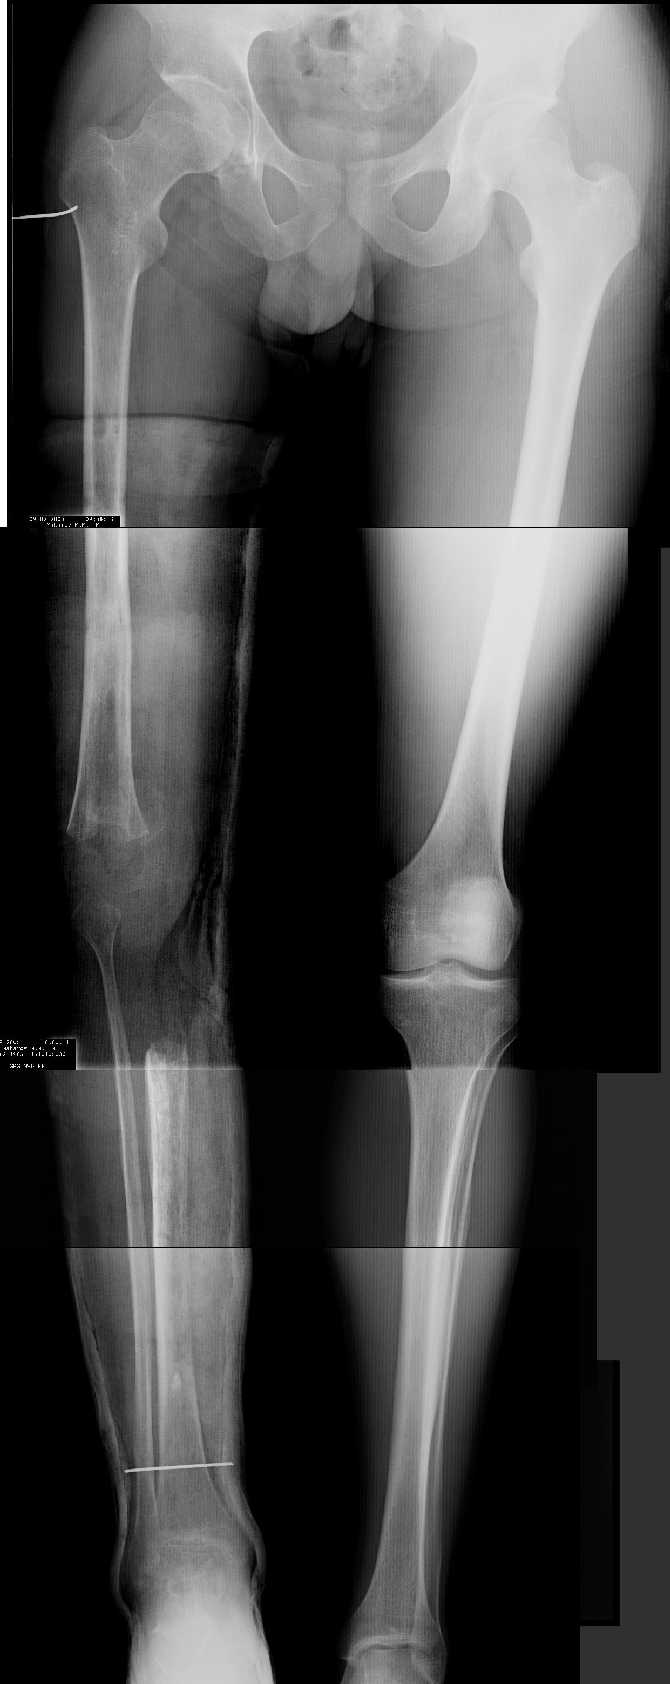

Даже по этим коротким снимкам видно, что варусная деформация на уровне бедра. Хотя для полноценной оценки оси сделать надо снимок всей конечности, от таза до стопы. Наклеить метки на кожу, по которым сделать склейку. И профиль бы тоже неплохо посмотреть.

Уважаемый Антон, при определении уровня остеотомии и величины коррекции руководствуемся, обычно, необходимостью обеспечить нормаль механической оси к середине опорной поверхности большеберцовой кости. Расчет производится по рентгенограмме (рентгенограммам) конечности под нагрузкой, которые визуализируют положение головки бедренной кости относительно таранной кости. На представленных рентгенограммах определить эти реперные точки (и заслужить Вашу зараннюю благодарность) не представляется возможным. Остается неясным с каким исходом сросся перелом правой большеберцовой кости. Складывается впечатление, что нанесены не механические, а анатомические оси. Исправлять проще за счет "минус - кость", но механически правильнее "плюс". Чтобы выполнить механические требования, иногда на ряду с угловой коррекцией (деваризация-экстензия, т.к. имеется не только разгибательная, но и сгибательная контрактура)необходимо медиолатеральное смещение.

Прежде всего необходимо выполнить рентгенографию в таком положении, как это показано на рис.

После этого представится возможность оценить ось и сравнитьеё с нормой Рисунки из кники Dror Paley - Принципы коррекции деформаций. Этой теме посвящены 800 страниц. Хотя, учитывая контрактуру, это исследование не будет исчерпывающим.

имеется S-образная деформация бедра на фоне "многооскольчатого

перелома правой бедреннойљ кости на границе средней и нижней трети со смещением"

(хотя "длинные" снимки конечно же не помешали бы...)

1. Иллюстрации - во вложении.

Два бедра после эндопротезирования.

Авторы операции долго думали почему больная хромает.

Сдклали снимок - одна нога короче почти на 3 см.

Здоровый человек и то будет хромать.

2. Другой пример - дефект после инфицирования коленного эндопротеза.

Предполагалось, что величина дефекта 11-12 см. Так получается, если

сделать снимок только области коленных суставов. Определить

укорочение сложно, так как нога просто болтатется.

Сделали снимок "от и до" - величина дефекта 17 см.

Правда эта иллюстарция сделана на цифровом рентгеновском аппарате.

Больной стоит, а трубка передвигается сверху вних, последовательно

выполняя рентгенограммы. В данном случае - 4 штуки.